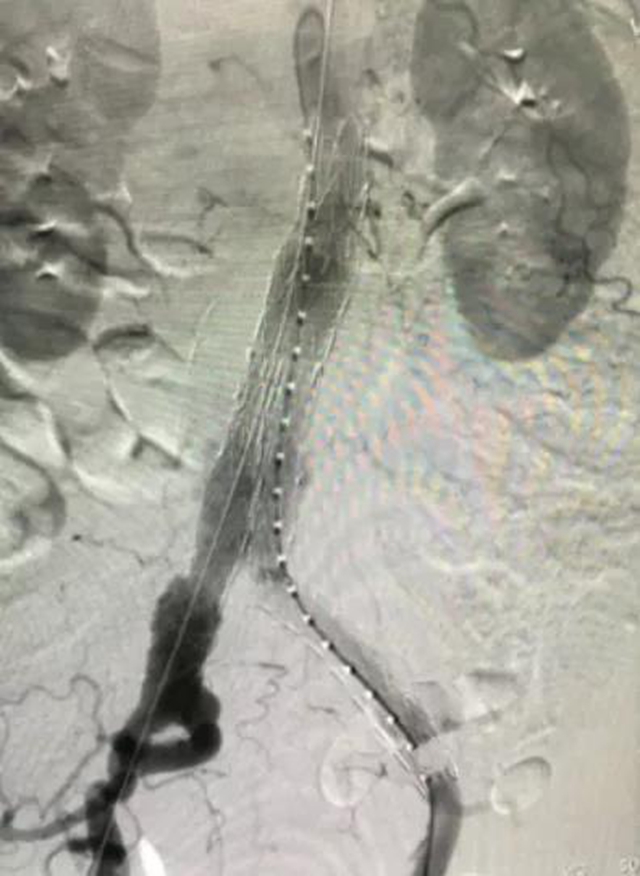

支架置入后

该手术通过腹股沟处的股动脉运用导丝导管技术,在穿刺孔将封装压闭的人工血管支架输送到瘤体位置,然后进行释放锚定,血流将通过人工血管走行。在紧张有序的氛围下,手术取得了圆满成功。

术后,患者平安返回病房,第一日恢复正常饮食,第三日可下床活动,第五日顺利出院。